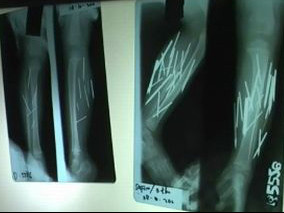

Một vài tháng trước đó, cô bé thường xuyên kêu khóc vì đau chân. Cha mẹ Safirah đã đưa cô tới bệnh viện để chụp x-quang. Sau khi có kết quả, các bác sĩ rất ngạc nhiên khi phát hiện những dị vật giống như đinh và kim trong bàn chân của cô bé.

Có 27 vật thể lạ được phát hiện trong chân cô bé. Các bác sĩ đã tiến hành loại bỏ thành công 26 vật thể. Cái cuối cùng ở trong một khu vực quan trọng, có thể gây tổn hại đến dây thần kinh cột sống nên chưa thể lấy ra được.

Các nhà khoa học không thể lý giải vì sao những kim loại này “chìm” trong cơ thể cô bé. Chân Safirah không hề có vết sẹo hay bất cứ tổn thương nào.